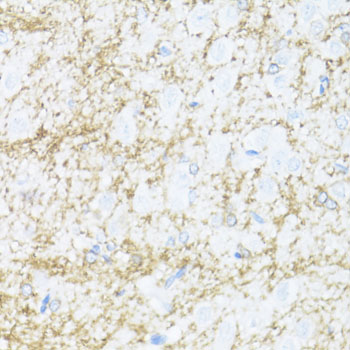

Immunohistochemistry of paraffin-embedded rat brain using CNP antibody at dilution of 1:100 (40x lens).

Immunohistochemistry of paraffin-embedded mouse spinal cord using CNP antibody at dilution of 1:100 (40x lens).